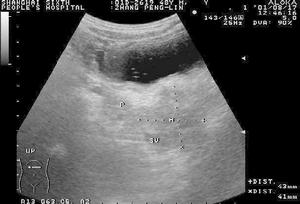

(2)B超:費用較CT低,敏感性和特異性也較高。可作為CT檢查的補充。